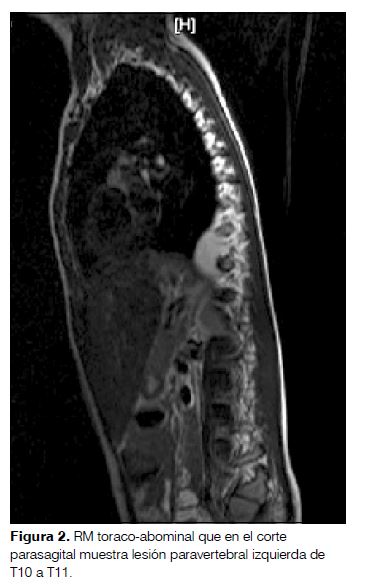

Comienza con irritabilidad, decaimiento y trastornos del sueño, agregando a las 48 horas ataxia con marcha inestable, aumento de la base de sustentación, alteración en la coordinación de miembros superiores y temblor cefálico. Ingresa en el Hospital de Salto presentando progresión de su sintomatología con pérdida de la bipedestación y sedestación independiente, alternancia de irritabilidad-somnolencia y vómitos reiterados. Se le realiza tomografía computada (TC) de cráneo (que fue normal) y punción lumbar con estudio del líquido céfalo-raquídeo. El estudio citoquímico fue normal, el virológico para virus de la familia herpes y enterovirus fue negativo. Se traslada al Centro Hospitalario Pereira Rossell donde se comprueba opsoclonus y polimioclonías (puntaje de la escala de SOM: 13/15). Con el planteo de SOM se inicia tratamiento con metilprednisolona e IgIV. Se realiza TC tóraco-abdómino-pélvica y resonancia magnética (RM) que muestran una lesión paravertebral izquierda de T10 a T11 que realza intensamente con el contraste, sin compromiso vertebral ni del canal raquídeo, compatible con el diagnóstico de neuroblastoma (figuras 1 y 2). El mielograma y el centellograma óseo con tecnecio 99 fueron normales.

Realizado el diagnóstico de SOM y, dado que en 45% de los casos se asocia a neuroblastoma, se debe proceder a la búsqueda del mismo(5). El protocolo de screening incluye: RM o TC de alta resolución de tórax, abdomen y pelvis, en los casos en que presentan un síndrome de Horner hay que realizar también imagen cervical; dosificación urinaria de catecolaminas (ácido vanilmandélico y homovanilmandélico) y centellograma con I123-metilodobenzilguanidina (MIBG)(1,6,7,9). En nuestro caso la TC y la RM evidenciaron la presencia de un neuroblastoma torácico, localización descripta como más frecuente (55%), sin evidencias de diseminación en el centellograma. Como el SOM puede preceder la aparición del neuroblastoma, de no encontrarse al momento del diagnóstico se recomienda continuar su búsqueda realizando RM cada 6 meses por 2 años(4). Realizado el diagnóstico del neuroblastoma se impone su tratamiento oncológico específico: cirugía y/o quimioterapia. Los síntomas neurológicos no necesariamente mejoran con la resección del tumor observándose solo en 1/3 de los casos y por lo tanto es necesario un tratamiento sintomático. Los fármacos más frecuentemente utilizadas son inmunosupresores e inmunomoduladores(3,10).